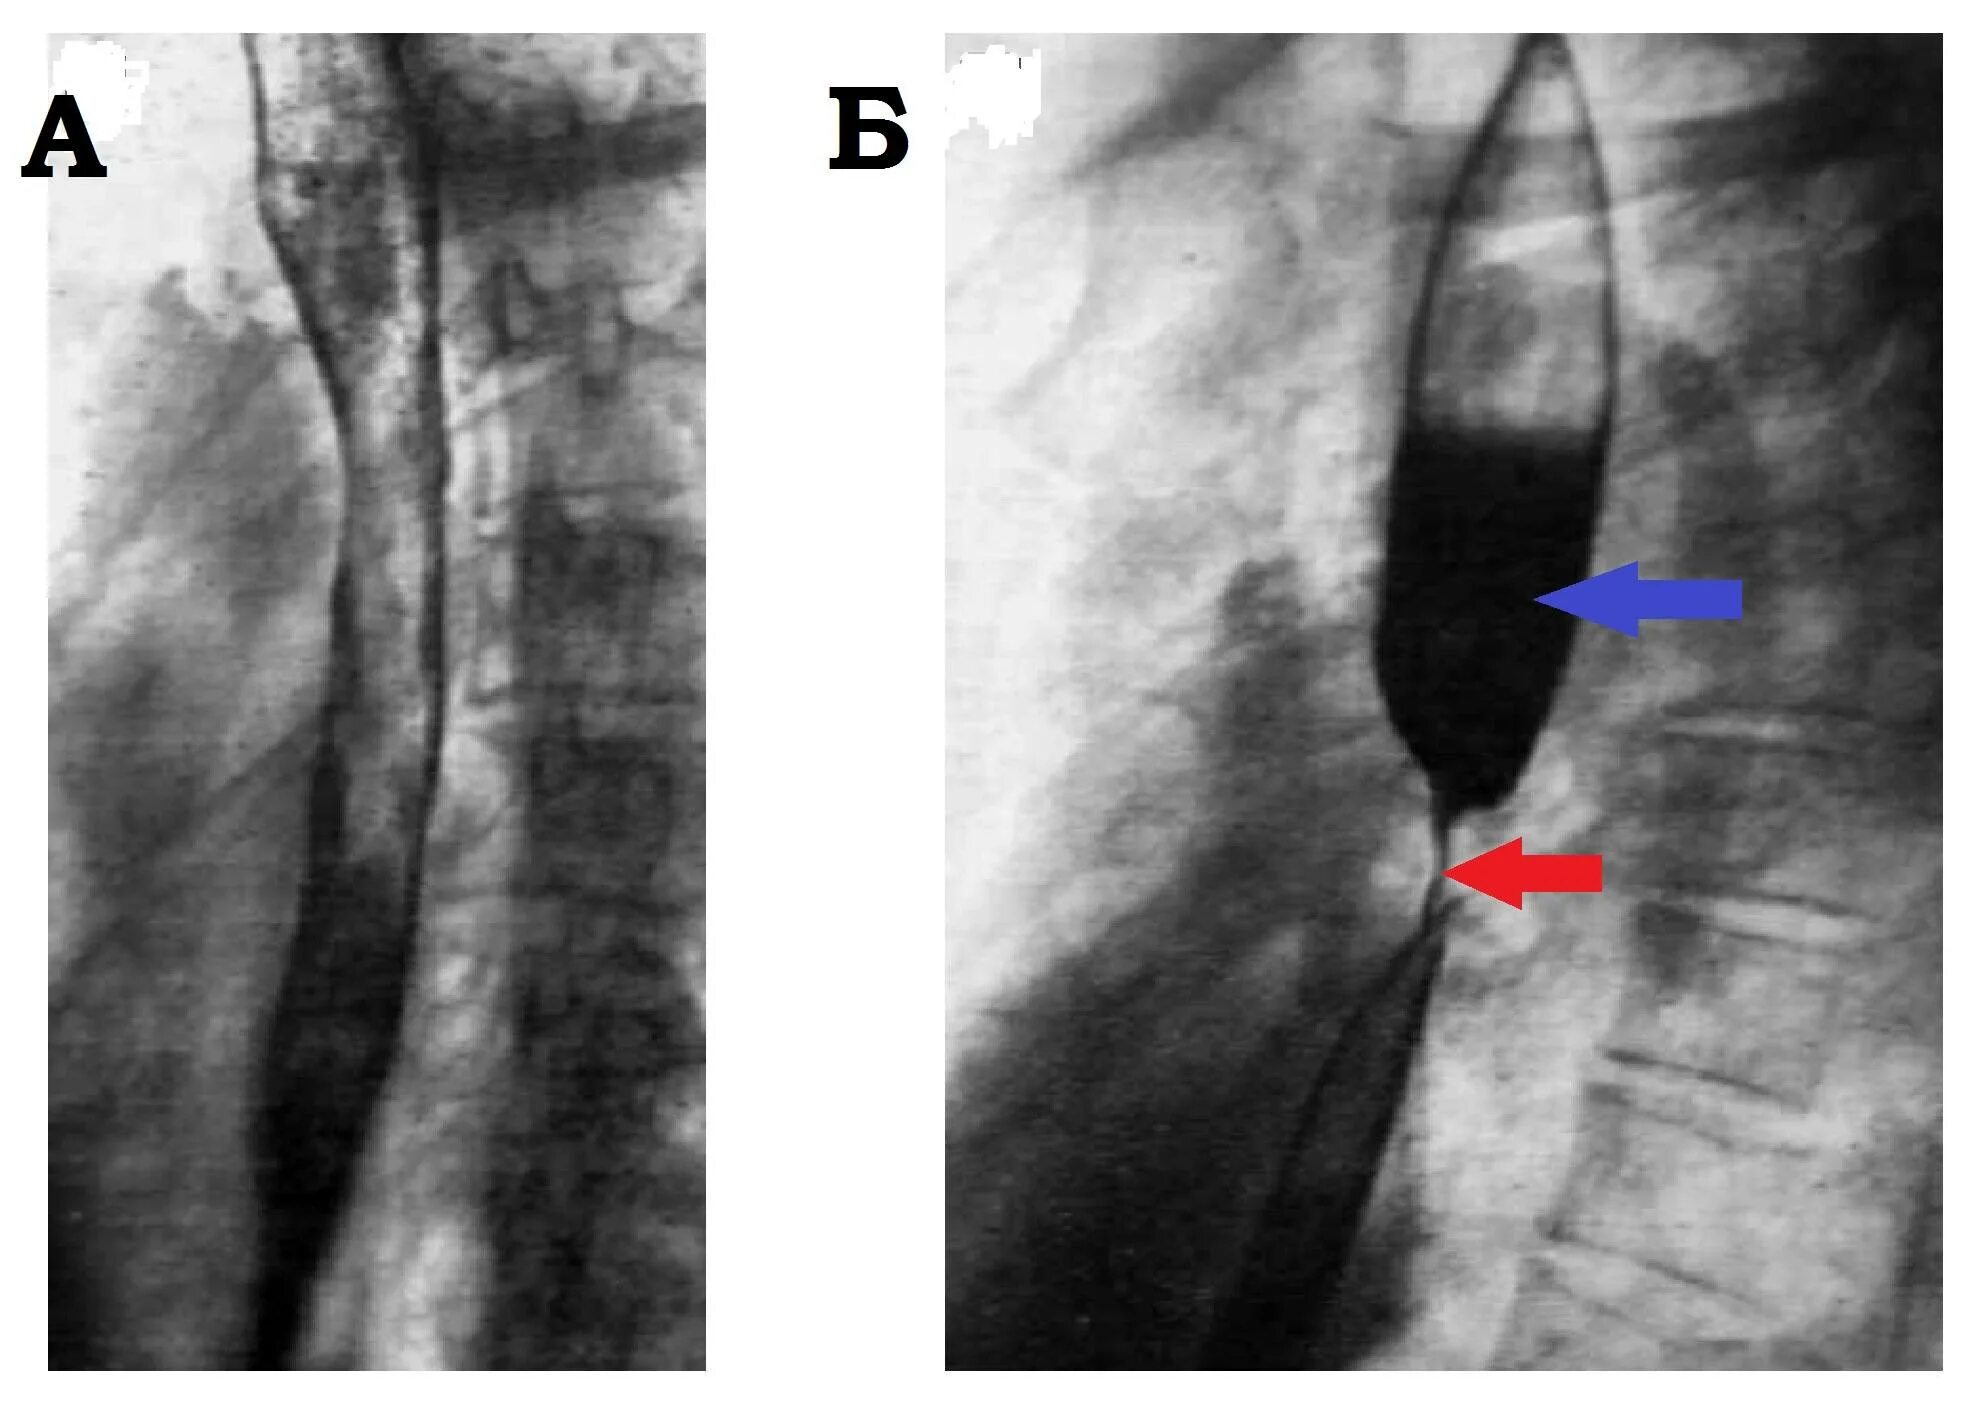

Стеноз пищевода симптомы